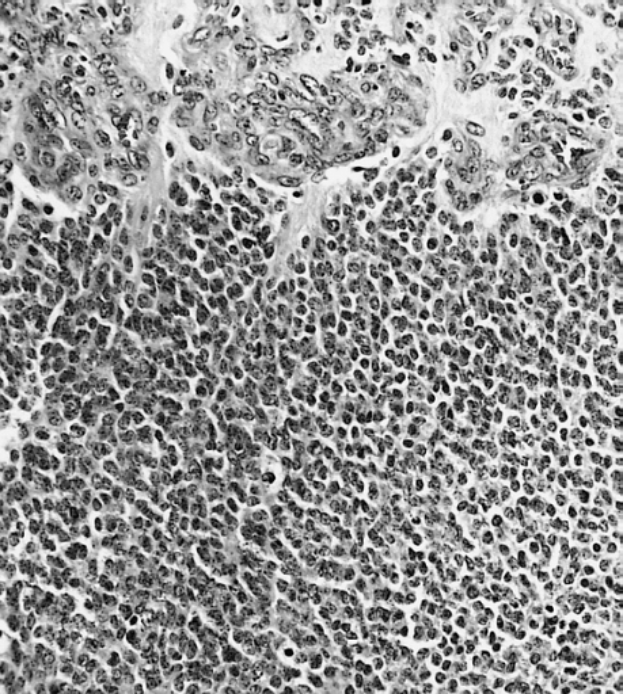

Ein schwarz-weißes mikroskopisches Bild einer kleinen Zellgruppe, die mit Anti-PFA1-Antikörper und BSA gefärbt ist.Klaus-Dieter Stahr

Phaeosynt spezialisiert sich auf die Herstellung von Antikörpern aus Kieselalgen (Diatomeen), einer Mikroalgenart. Im Gegensatz zu herkömmlichen Verfahren, die auf tierische Zellen angewiesen sind, spart dieser Ansatz Energie, Platz und Transportkosten. Da Kieselalgen bei niedrigeren Temperaturen wachsen, ist das Verfahren deutlich nachhaltiger.